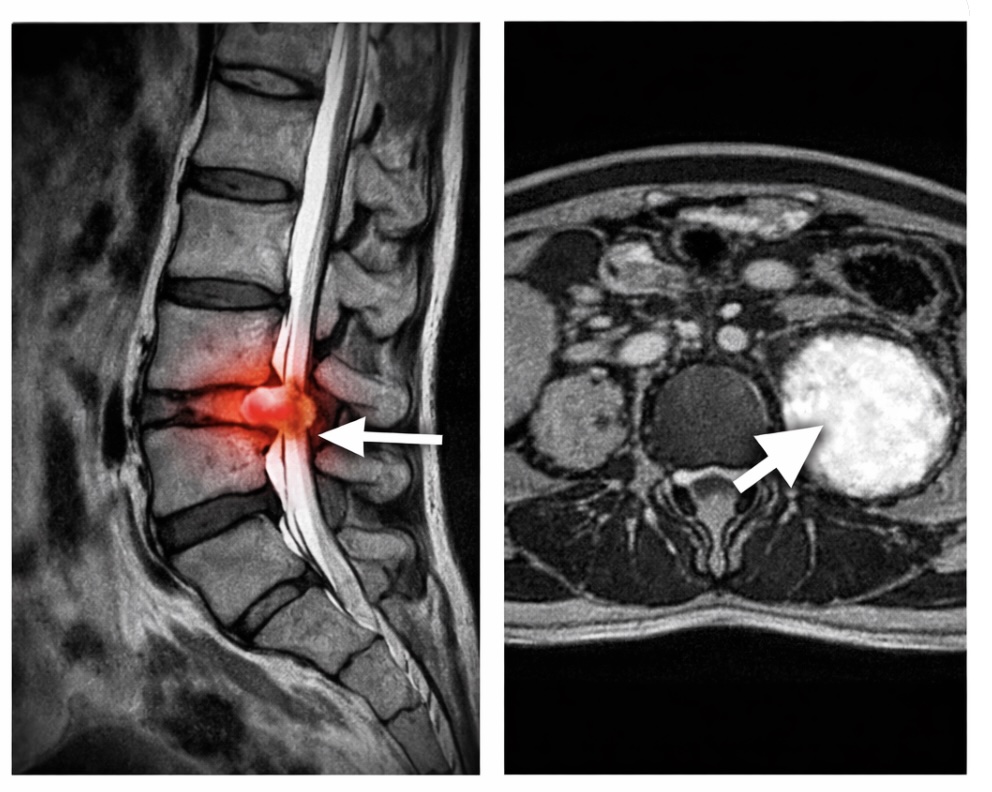

腰痛は大きく2つに分類されます。特異的腰痛

レントゲンやMRIなどの画像検査で、痛みの原因(骨折、椎間板ヘルニア、腫瘍など)がはっきりと特定できるもの。

非特異的腰痛

厳密には「画像検査などで痛みの原因部位を特定できない腰痛」を指しますがはっきりと特定できるもの。.jpg)